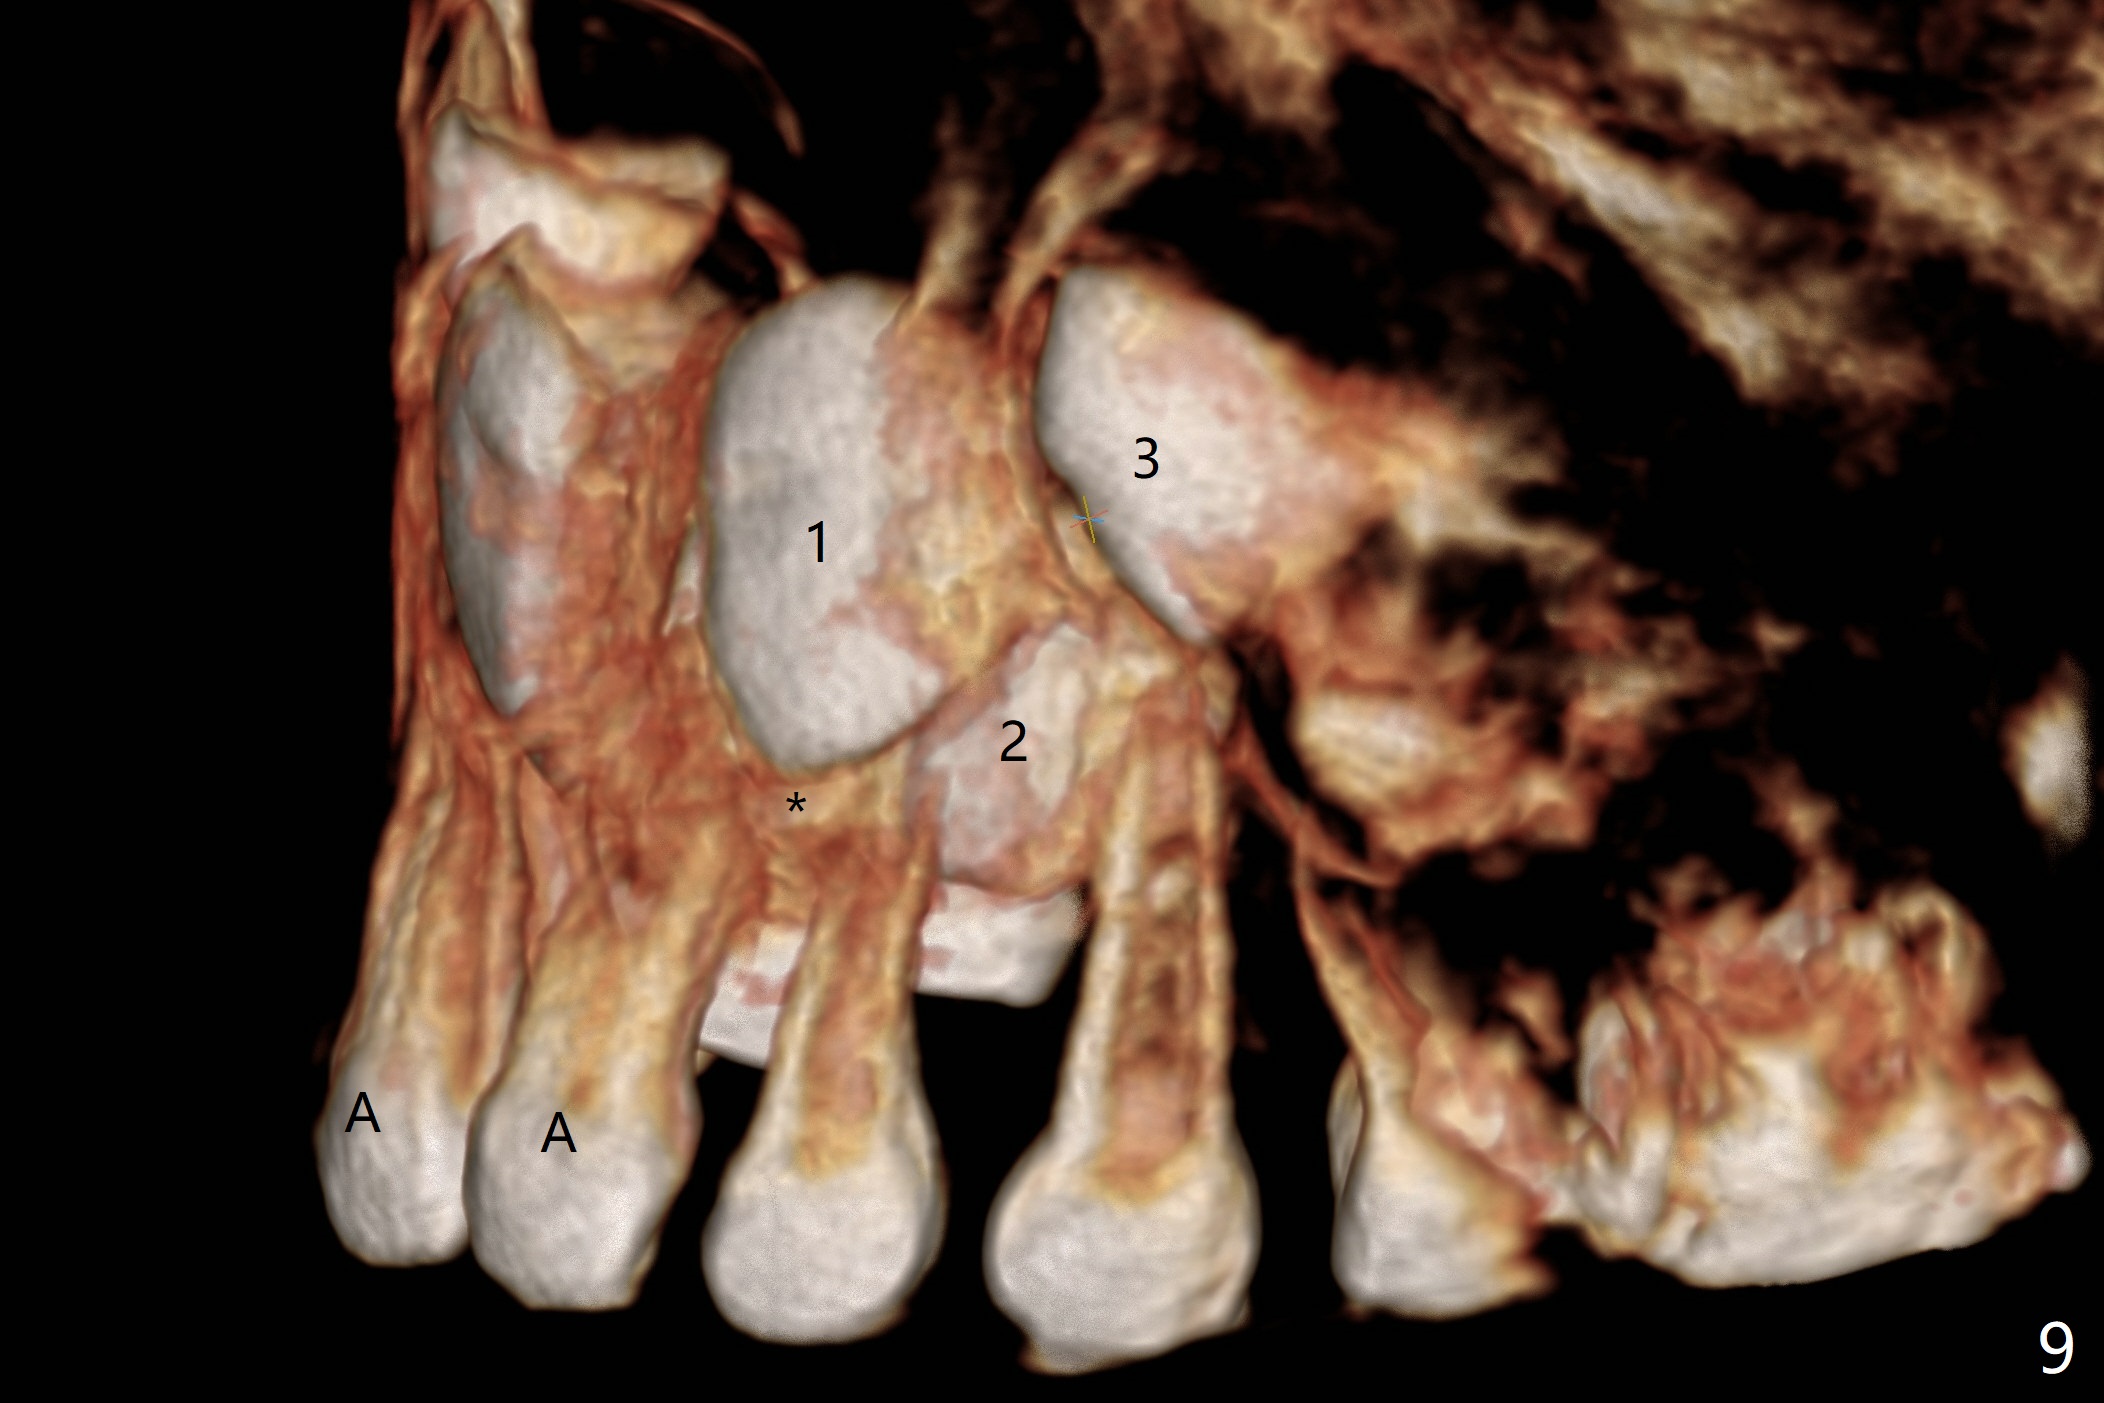

CBCT taken on 11/03/2017 confirms the findings mentioned above (Fig.2-4).  These 2 supernumerary teeth are close palatally (Fig.3 (for UR1), 4 (UL1)).

Reanalysis of 3 D images (Fig.7 (frontal view), 8 (posterior view), 9 (lateral view), 10 (lateral view with section) of CT taken 1 year 3 months earlier shows that the mesiodens (*) and the permanent lateral incisors (2) are palatal to the permanent central incisors (1) and canines (3) and the deciduous central incisors (A).  The supernumerary teeth do block the eruption of the permanent central incisors (Fig.10).